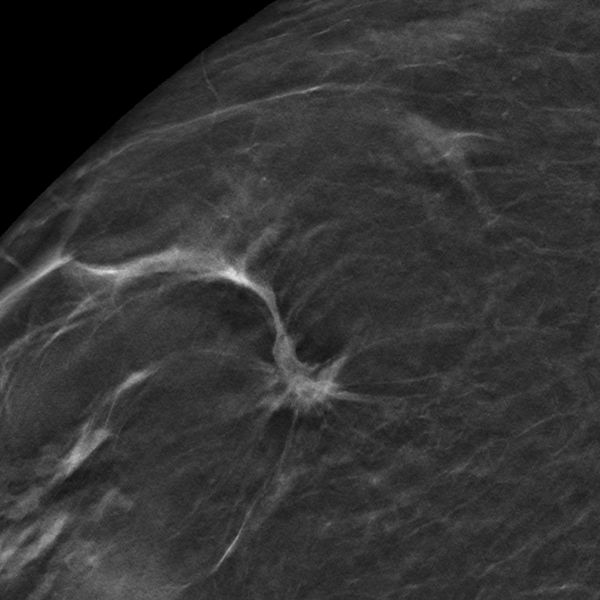

In der ToSyMa-Studie wurde die Kombination aus Digitaler Brust-Tomosynthese (DBT) – einer Weiterentwicklung der digitalen Mammographie – und sogenannten synthetischen 2D-Mammogrammen mit dem bisherigen Screening-Standard verglichen. Erste Ergebnisse aus der Studienphase 1 sind nun nachzulesen in der renommierten Fachzeitschrift „The Lancet Oncology“. Der Grund für das bessere Abschneiden der Kombi-Methode laut den Autoren: Der innovative Bildgebungsansatz reduziert die Wahrscheinlichkeit, dass überlappende Gewebestrukturen radiologische Zeichen für Malignität (Bösartigkeit) verdecken.

Studienleiter Prof. Walter Heindel, Direktor der Klinik für Radiologie des Universitätsklinikums Münster (UKM), und die Projektmanagerin der ToSyMa-Studie, Prof. Stefanie Weigel, danken den 100.000 Frauen, die an der Studie teilgenommen haben: „Nur durch ihre Beteiligung ist eine aussagekräftige Forschung möglich und dank dem Fördergeber, der diese große randomisierte Diagnostikstudie unterstützt.“ Die Deutsche Forschungsgemeinschaft (DFG) finanziert das Projekt mit mehr als 1,6 Millionen Euro bis zum Jahr 2025. Sie unterstützt damit das Ziel, die Frühdiagnostik von Brustkrebs weiter zu optimieren. Das ToSyMa-Team ist sich sicher: Die Weiterentwicklung der digitalen Mammographie zur Brust-Tomosynthese bietet eine Technologie, die durch die Berechnung von Pseudo-3D-Datensätzen potenzielle Gewebeüberlagerungen in der Brust reduziert und daher diagnostische Vorteile verspricht.